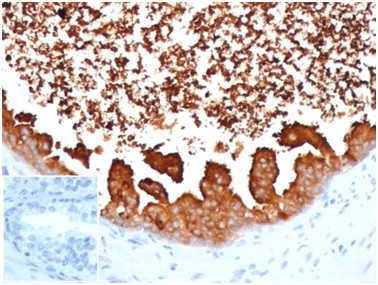

Lactotransferrin/Lactoferrin/LTF Antibody in Immunohistochemistry (Paraffin) (IHC (P))

Lactotransferrin/Lactoferrin/LTF Antibody (4057-MSM5-P0) in IHC (P)

Formalin-fixed, paraffin-embedded human prostate carcinoma stained with Lactotransferrin Mouse Monoclonal Antibody (LTF/4075). Inset: PBS instead of primary, secondary negative control. {{ $ctrl.currentElement.advancedVerification.fullName }} 验证信息 View more